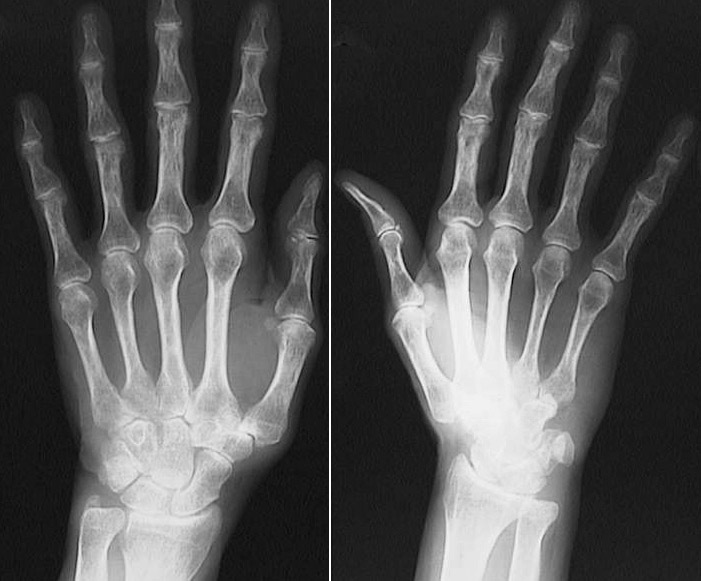

The two radiographic views seen here demonstrate changes of osteoarthritis of the left hand, with narrowing of joint spaces of the

distal interphalangeal joints

.